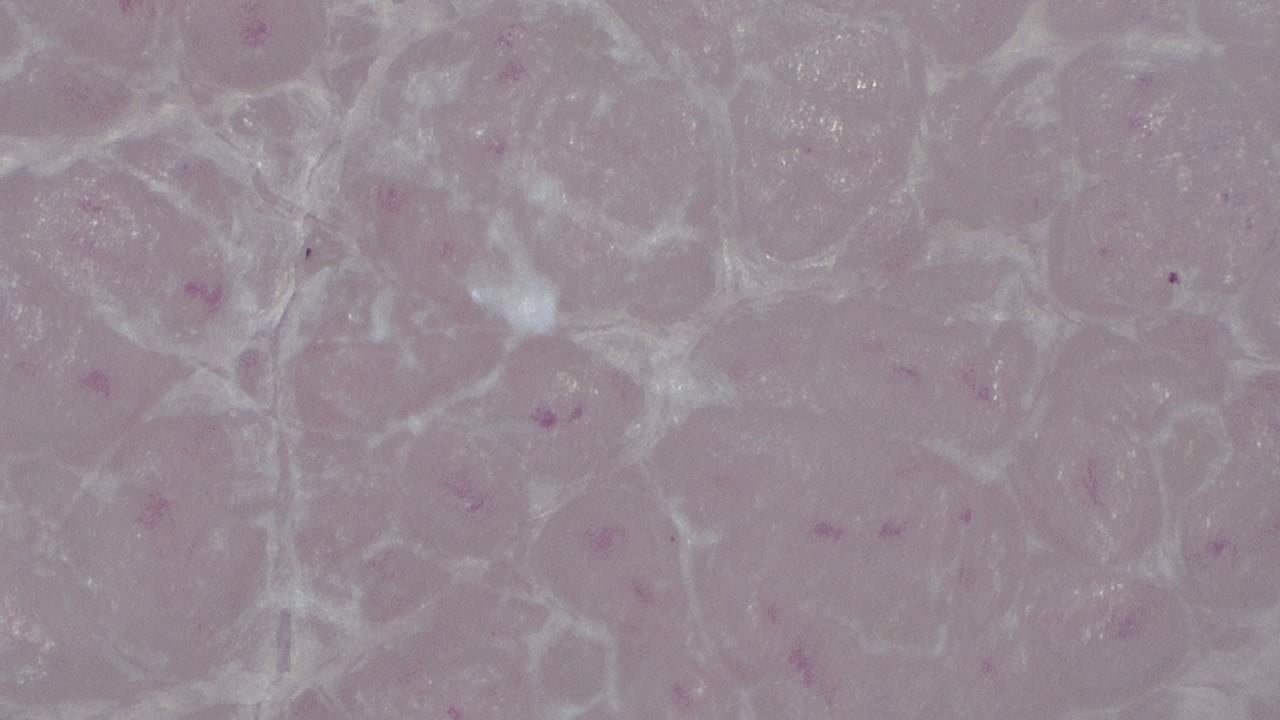

With variable magnification, it is possible to examine everything from superficial structures to deeper epidermal layers, identifying pigmentation patterns, abnormal vascularization, and textural changes that may go unnoticed to the naked eye.

- Visualization of dermal structures with up to 250× magnification

Image gallery

Click any image to enlarge